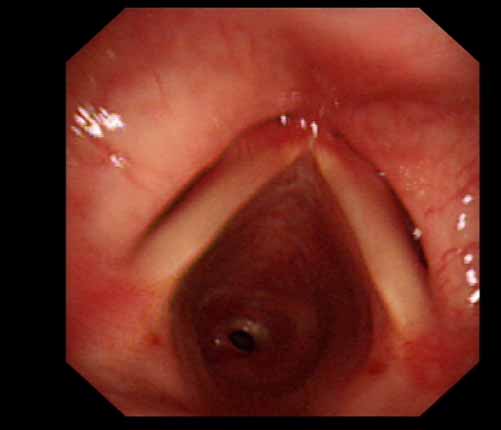

患者李某某,女,45歲,因氣管插管咳嗽、喘憋10天入院。頸部CT檢查示聲門下約20mm處氣管明顯狹窄,狹窄段長約26mm,最窄處直徑約4.4mm。支氣管鏡檢查見聲門下約2cm氣管呈漏斗狀縮窄,直徑約4-5mm,支氣管鏡無法通過。經科室討論,決定行電子支氣管鏡下氣管球囊擴張治療。與患者及家屬充分溝通并經三方見證談話簽署知情同意書后,在患者持續吸氧、局麻下,科主任于世倫主任醫師帶領治療小組為患者實行電子支氣管鏡下氣管球囊擴張術。手術過程順利,出血量很少,術后患者呼吸困難癥狀即可明顯緩解。10天后行二次擴張,患者日常活動無明顯喘憋,二次術后5天出院。

術前聲門下的漏斗樣狹窄口